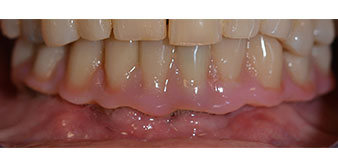

Die 64-jährige Patientin wurde mit einer Unterkiefer-Restbezahnung 38, 33 und 43 und einer klammerbefestigten Interimsprothese im Unterkiefer vorstellig (Abb. 1 und 2).